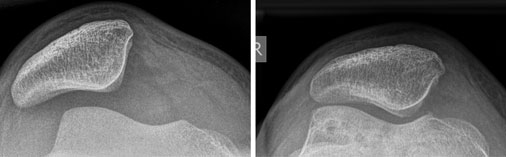

Bei Rezidivluxation oder chronischer Instabilität der Kniescheibe ohne höhergradige Deformität ist eine Rekonstruktion des innenseitigen Halteapparates als rein weichteiliger Eingriff ausreichend. Bei der MPFL-Plastik wird mittels einer körpereigenen (autologen) Spendersehne, ähnlich wie bei einer Kreuzbandoperation, eine Bandrekonstruktion des medialen Halteapparates der Kniescheibe durchgeführt.

Nach Verletzungen des Halteapparats der Kniescheibe läuft diese nicht mehr zentral in ihrem Gleitlager (links). Nach Stabilisierung mit einer körpereigenen Sehne hat die Patella wieder eine gute Position (rechts).